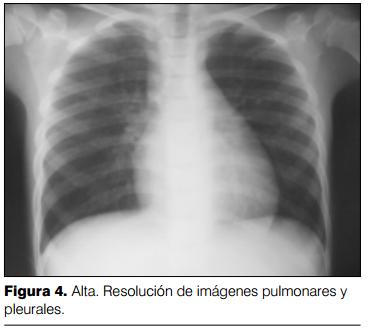

Pasó a sala de pediatría a los 10 días del ingreso, otorgándose alta al domicilio con mejoría franca desde el punto de vista clínico y radiológico (figura 4).